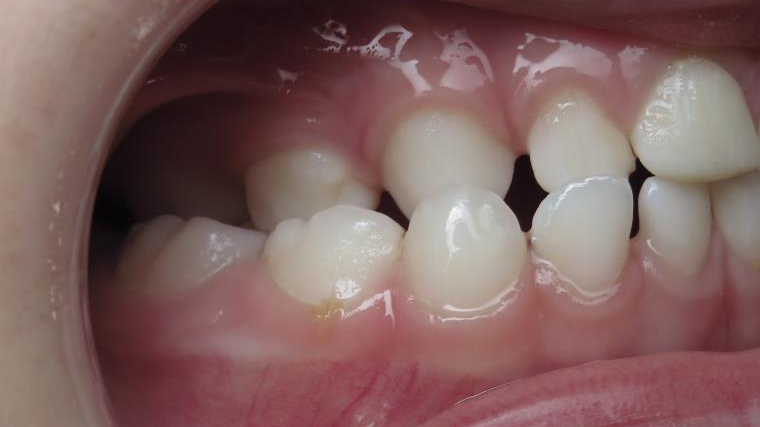

7.inversé droit 4 ans

inversion des dents postérieur coté droit